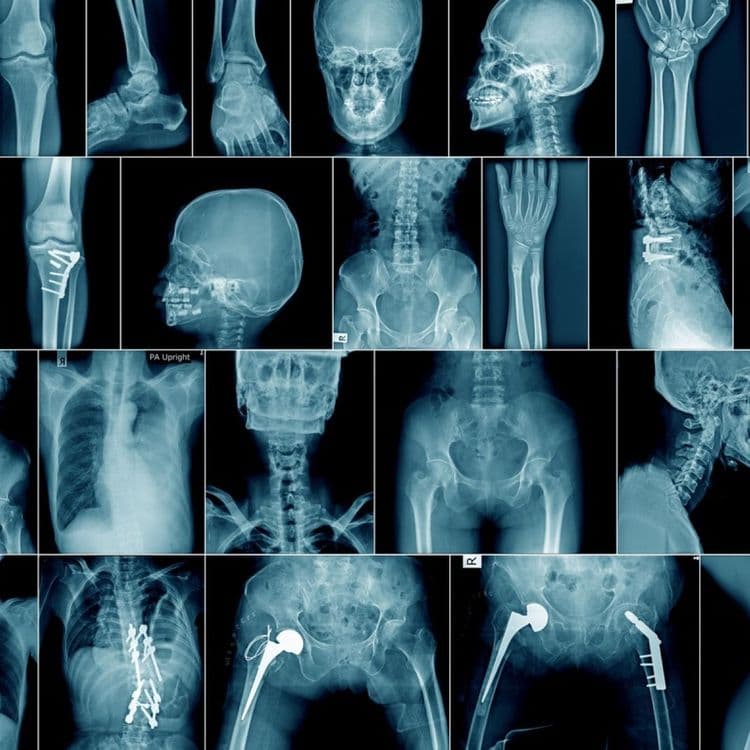

एक्स रे किरणांचे आजच्या मेडिकल सायन्समधील महत्व कुणीही नाकारू शकणार नाही. एक्स रेचा उपयोग शरीराच्या आतल्या भागातील बिघाड शोधण्यासाठी केला जातो हे तर सर्वांना माहीत आहे. पण एक्स रेचा उपयोग कॅन्सरसारख्या आजार शोधण्यासाठी देखील केला जातो. तसे एक्स रेचे अनेक उपयोग आहेत. पण आज आम्ही तुम्हाला एक्स रेचे फायदे नाही, तर या एक्स रेच्या शोधामागील गोष्ट सांगणार आहोत.

रोन्टजेन यांनी एक फोटो फिल्म डेव्हलप केली. त्यांना आता दिसून आले की, प्लेटवर हाताचे हाड स्पष्टपणे दिसत आहे. तसेच त्यांच्या चारी बाजूला अंधारल्यासारखे त्यांना दिसले. त्यांनी पुन्हा त्यांच्या पत्नीवरही हा प्रयोग करून बघितला. एखाद्या जिवंत व्यक्तीचा हा पहिलाच एक्स रे होता. या एक्स रेत त्यांच्या पत्नीची बोटे तसेच हातातली अंगठी देखील त्यांना स्पष्टपणे दिसली.